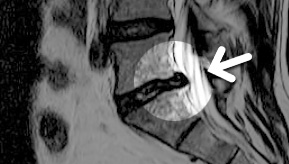

MRI

㸮 , ٸ ʹ

, Ƹ, ߰ ļ

Ȱ ް

ħϴ ũ ؽ ɾҡ

㸮 Ͱ Ұߴ

MRI ġ

ȯڰ ġı

ȸŰ渶 ġ